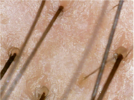

since i was 19 i was loosing my hair with a white bulb at the end of it. About a year and a half ago I went to the dermatologist about my hair loss. She checks my hair with a otoscope for about 10 seconds and does a pull test and tells me i have alopecia and dandruff. Then i tell her that hairs that fall have this white bulb at the end of it and its been going on since i was 19 tells me that i have telogen effluvium. then i get prescribed finasteride, ketoconazole 2% shampoo, and minoxidil 7%. Now 23 still use finasteride, ketoconazole 2% shampoo but not minoxidil 7% it irritated my scalp did use minoxidil 5% but stop after 5 months saw no improvements. About 3 month still loosing lots of hairs but do see less falling and its been going like that since then but recently i started loosing lots of hair again. I'm pretty sure I have chronic telogen effluvium (my scalp is very visible when wet and oily) but I also think I'm loosing my hair because of sebum. My hair gets oily through out the day and after I sleep and wake up I'm just covered in oil I do shower every morning. After I shower I let my hair dry and I comb it and there's just tons of hairs falling out nothing new but now its lots more. I'm posting pictures of my scalp and the white bulb if anybody has any ideas what's going on on my scalp.